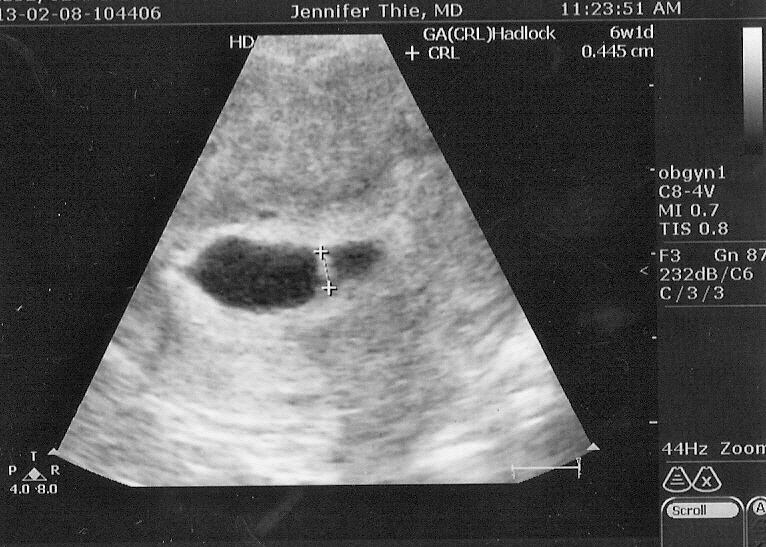

Today we got to go in for our second ultrasound at 6w3d. I had to be weighed at this visit (YIKES!) and then was asked to empty my bladder, undress from the waist down, and wait for the doctor to come in to do the ultrasound. As a veteran of many, MANY a vaginal ultrasound now, I know the trick is to undress and dive under the tiny square of paper given to protect your modesty as quickly as possible since the doctor could come walking through the door anywhere from 15 seconds to 15 minutes after the instruction to undress is given. So I make quick work of undressing as Eric guards the door and then we assume our positions to begin waiting for the doctor at around 10:40. We talk about our nervousness regarding the last week's spotting, how anxious we are to see the heartbeat and how we are both slightly concerned we won't see one. We talk about the lunch Eric is going to after the appointment, when our next doctor's appointment is likely to be, etc, etc, etc. Around 11, after 20 minutes of sitting there half naked on a somewhat cold day in a not quite warm room, my conversation starts to turn to how long the doctor is going to take. I tell Eric if she is not in by 11, I will go out half naked to find her. By 11:10, I am growing QUITE impatient and trying to convince Eric to go check how long it is going to be. By 11:15, I insist he needs to go tell them my lady parts are developing signs of hypothermia and to ask if I can just wait with my pants on but FINALLY, at 11:18, the doctor comes in and I swallow my mounting irritation to discuss my spotting concerns and get the ultrasound started. Within seconds, the gestational sac comes up on the screen (Whew, still pregnant!) and a quick zoom in shows our jellybean with the cutest little flickering heartbeat and all my irritation about the delay and the indignity of my pants-less situation melts like summer snow.

We have a baby and its heart is beating.

| (The baby is between the plus signs...you can't see its heart beating but trust me, it is) |

We have been here before and I know that this is no guarantee that this baby will stay with me, but for this moment, I am pregnant and the baby looks as perfectly perfect as any mother could dream. I am indescribably happy and schedule my final appointment with the RE's office for Feb 21st (8w2d) at 3:30 pm.